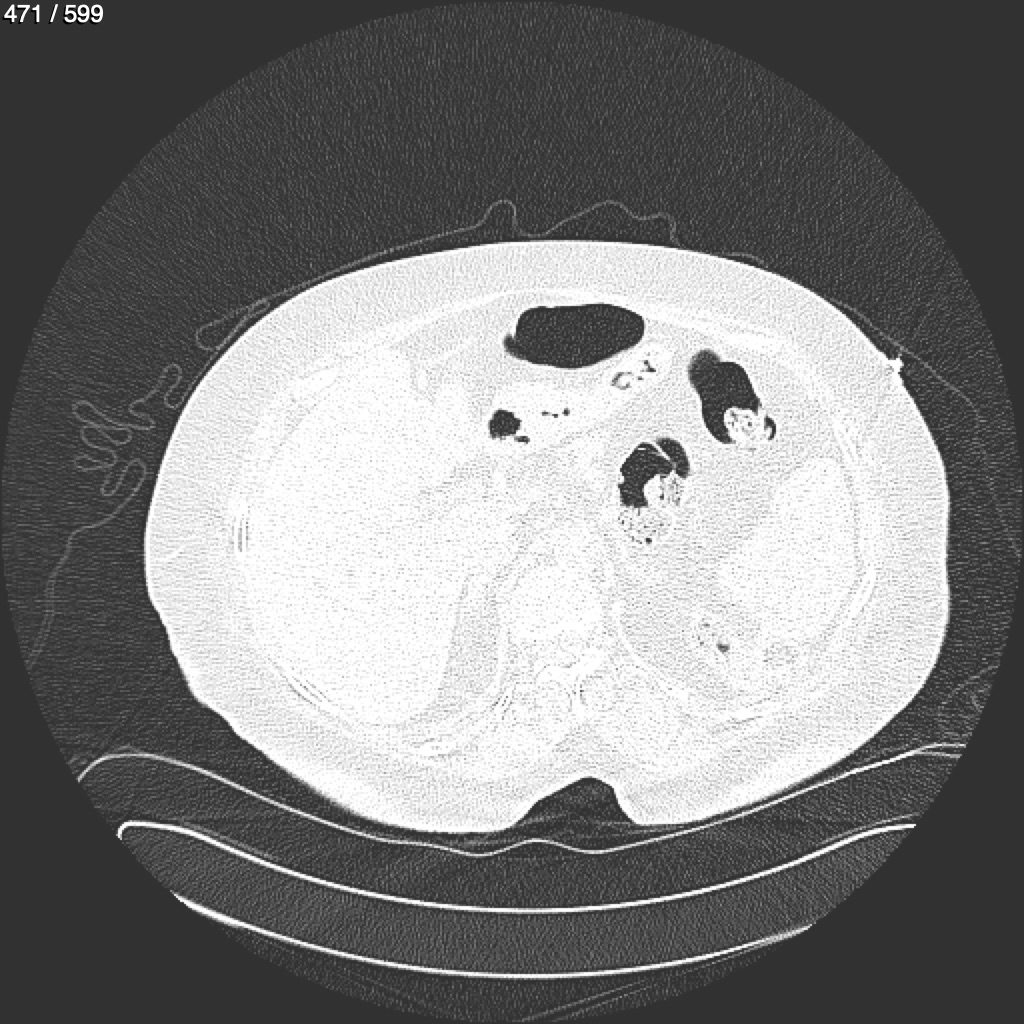

Home G​l​o​r​i​a​ ​G​l​a​d​y​s​ ​B​e​a​s​l​e​y​ ​-​ ​T​ó​r​a​x​ ​T​o​r​a​x​_​S​i​m​p​l​e​ ​(​A​d​u​l​t​o​)